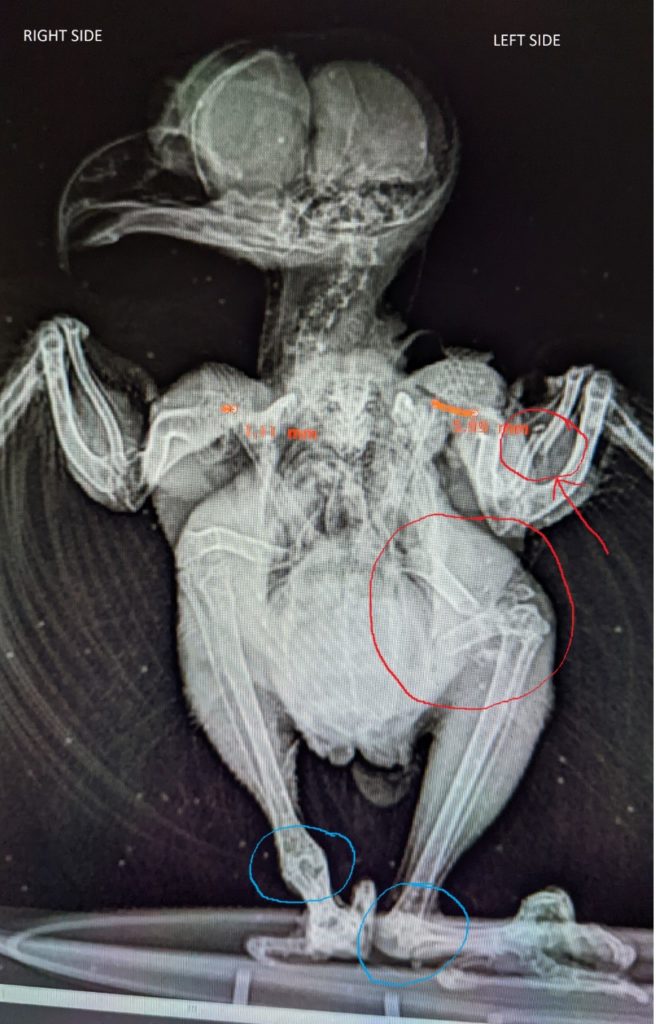

Consider this: a human body colliding with a vehicle moving at 31-32 MPH has a 50% chance of severe injury and a 25% chance of death. Imagine the pain a small body feels during a similar collision. But we don’t have to imagine; we can see it in the radiograph here. This tiny being, an eastern screech owl weighing just 183 g (6.5 oz) sustained multiple severe fractures, dislocations, soft tissue injury and a detached retina. And yet, somebody took it home to “nurse it back to health” with its little bones grinding one on the other, its tiny battered, bruised body in shock, its organs probably bleeding into its abdomen. And they fed its broken body, because bodies want to eat, and if it’s eating it’s OK, right?? But there was no pain relief, no stabilization of the broken parts, no supportive care other than offering food because the ‘savior’ did not know what they were looking at and made no attempt to find out.